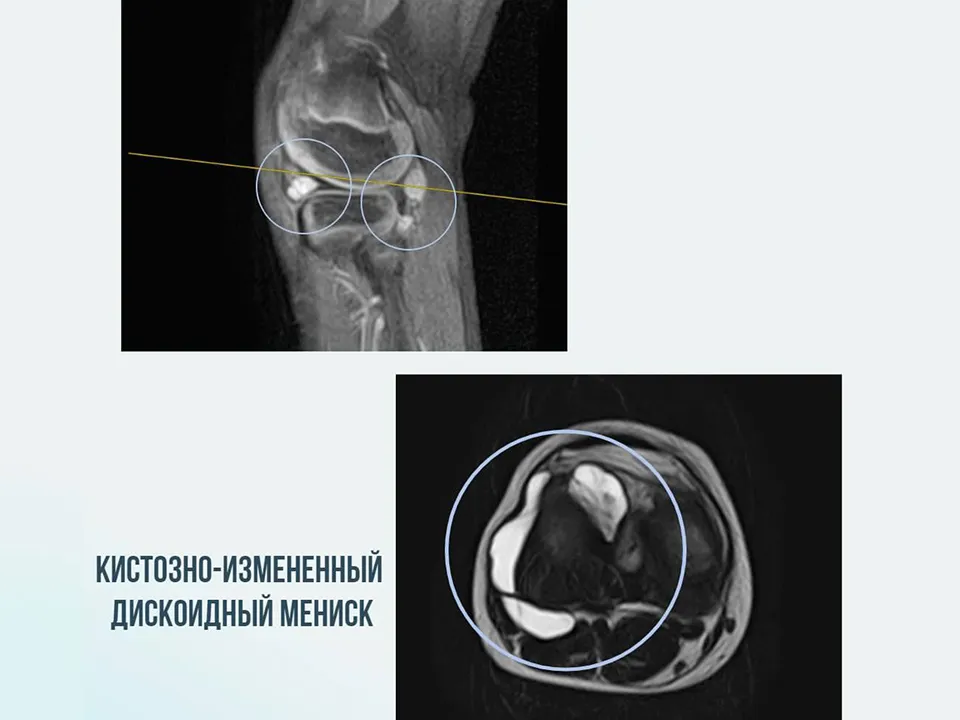

В МОДКТОБ поступил мальчик в возрасте восьми лет с жалобами на сильную боль в колене. Движения мальчика были скованы и наблюдалась сильная хромота. Об этом сообщили в Министерстве здравоохранения Московской области.

Родители сообщили, что неприятные ощущения в колене появились у ребенка еще в два года, но сейчас усилились и стали невыносимыми. Проведя необходимые обследования, врачи обнаружили у мальчика дискоидный мениск.

«Это врожденная аномалия развития, при которой хрящевая прослойка коленного сустава изменена. В данном случае заболевание было осложнено наличием кист в суставе. Мы провели реконструктивную артроскопическую операцию, в ходе которой устранили кисты и сформировали правильную анатомическую форму мениска. Операция прошла успешно», — прокомментировал заведующий отделением № 3, врач травматолог-ортопед Сергей Катин.